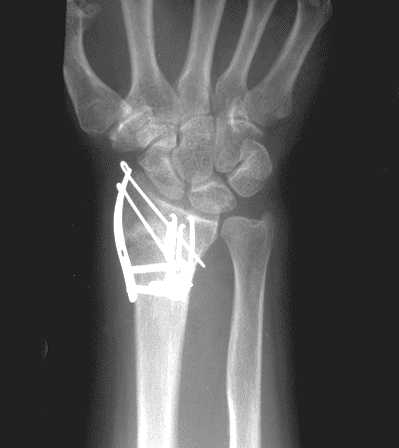

Case 1 Postop